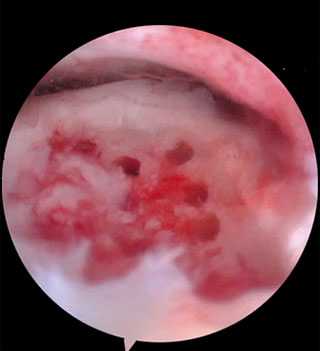

Методика заключается в удалении всех отколовшихся фрагментов хряща и подлежащей некротизированной (умершей) кости. Если в кости под хрящом имеются кисты, они вскрываются и специальным образом обрабатываются. Затем особым интструментом выполняется микро перфорация кости. Это приводит к высвобождению факторов роста, которые заполняют дефект хряща таранной кости.

Происходит стимуляция образования новых сосудов, в остеохондральный дефект выходят стволовые клетки костного мозга таранной кости, и он в последующем заполняется хрящом.

Во время операции снижается внутрисуставное давление на хрящ, что приводит к блокированию стимуляции нервных окончаний и уменьшению выраженности болевых ощущений у пациента.

Хорошие и отличные результаты отмечены у 86% пациентов.

В ходе операции производят освежевание с помощью острого бора основания дефекта хряща таранной кости до появления кровоточащей поверхности

По завершении подготовки ложа таранной кости, хирург перемещает астроскоп в коленный сустав, где выполняется забор остеохондральных трансплантатов из мыщелков бедра.

Трансплантаты забираются с помощью трубчатых полых сверил, которые обеспечивают забор трансплантата точного диаметра и длины.

Далее переходят обратно на голеностопный суставе, где в области дефекта хряща таранной кости, специальными сверлами формируется костный каналы соответствующий трансплантатам из коленного сустава по длине и диаметру. В завершении трансплантаты взятые из коленного сустава впрессовывается в сформированный в таранной кости каналы и моделируется по уровню суставной площадки.